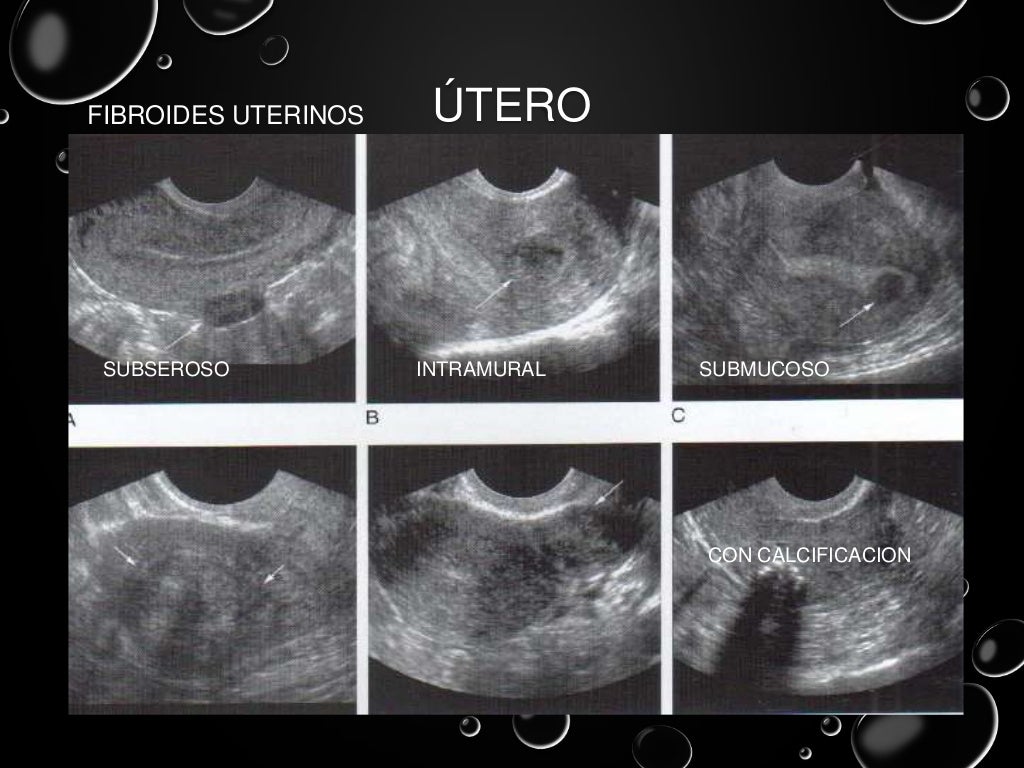

ultrasonido pelvico salud digna El precio del ultrasonido pélvico en salud digna laboratorios puede variar ya que hay varios tipos de ultrasonido que componen la zona pélvica. Ultrasonido de abdomen con un costo de $105. Las imágenes ecográficas del ultrasonido pélvico pueden también ayudar a determinar posibles quistes ováricos o fibromas uterinos, así como cáncer ovárico o uterino. Un ultrasonido o ecografía es un procedimiento seguro que utiliza ondas de sonido no audibles para el ser humano, las cuales escanean diferentes partes del cuerpo, con el propósito de crear una imagen del interior. El ultrasonido pélvico es primordial para diagnosticar el origen del dolor pélvico, sangrado anormal, u otros problemas menstruales. En un ultrasonido obstétrico, se explora tu abdomen y cavidad pélvica durante el embarazo, con lo que es posible. Un ultrasonido intravaginal también puede ayudar a diagnosticar problemas de fertilidad en la vejiga, los riñones y la cavidad pélvica. Ultrasonido 4d con un costo de $230.

Ultrasonido pelvico

Source: es.slideshare.net